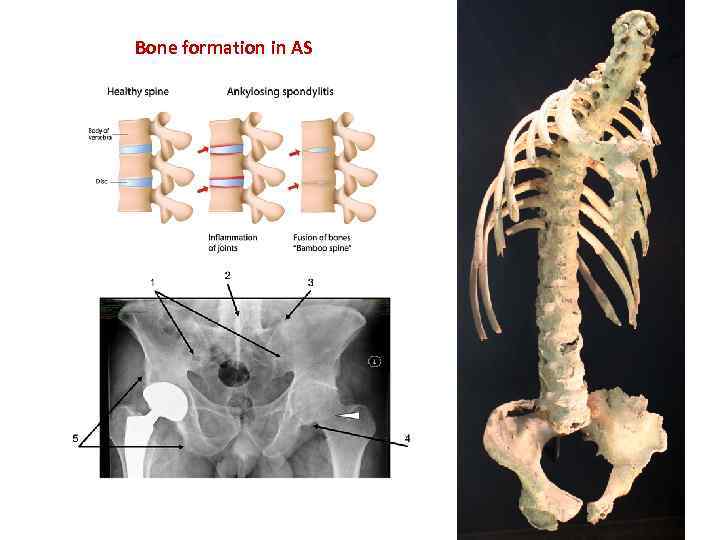

Bone formation in AS

Spine

Sacroiliac joints

Spine